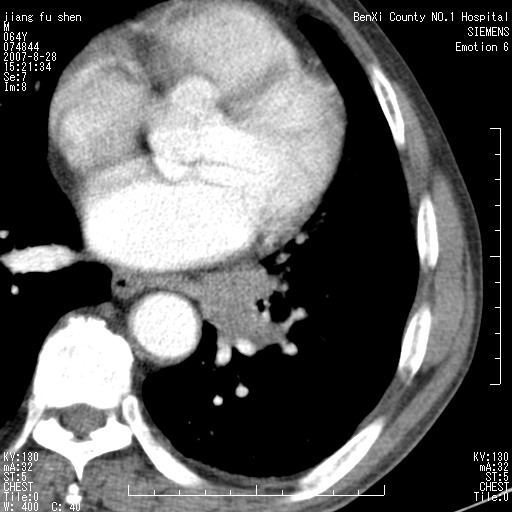

男、64、咳嗽、发烧一周、左肺呼吸音稍弱。既往肺结核,右手结核。

本次扫描患者未带原片,左肺下叶发现病灶。左肺上叶空洞,5组淋巴结肿大,1cm左右。

平扫20-33hu

增强31-33hu

1分半44-52

2分55-67

左肺下叶前内基底段支气管明显偏心性狭窄,周围分叶状肿块,伴有阻塞性肺炎,支持肺癌可能性大。